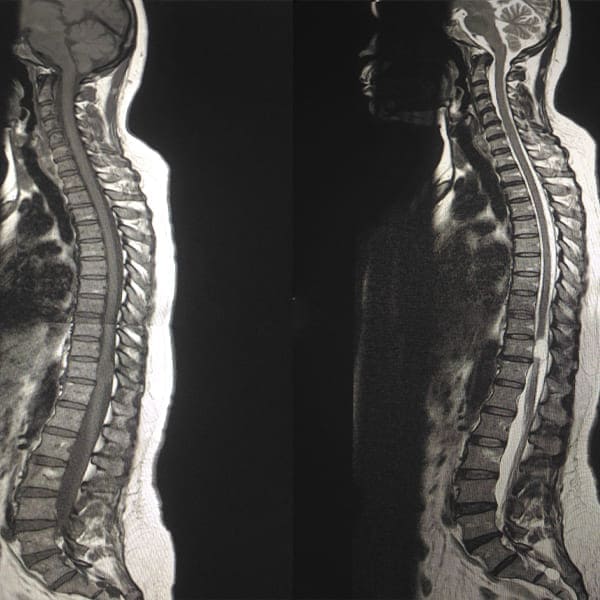

Durante una valoración integral, el Dr. Villanueva utiliza tecnologías de diagnóstico de vanguardia, incluyendo resonancia magnética (MRI), tomografía computarizada (CT) y radiografías, para obtener una imagen completa de la estructura de la columna. Esto permite identificar con precisión problemas como hernias discales, estenosis espinal, deformidades y otras patologías que pueden requerir intervención.